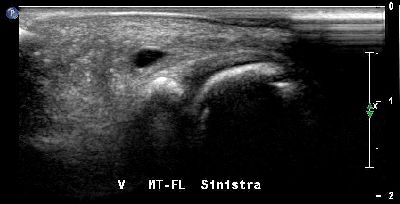

Depressione calcaneare Depressione calcaneare 01

Depressione calcaneare depressione calcaneare 02